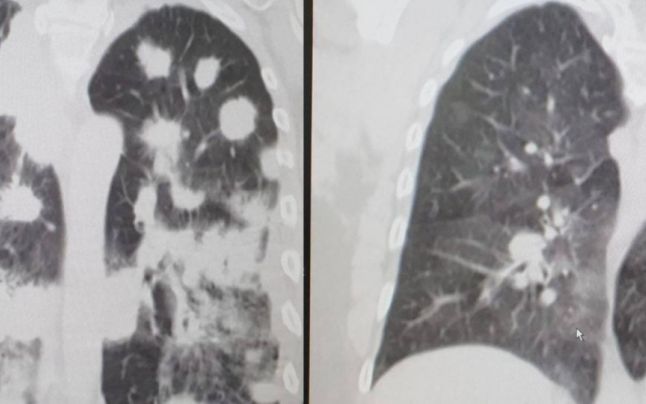

Leziunile pulmonare în cazul unui pacient care are şi alte boli (stânga), respectiv în cazul unui pacient fără comorbidităţi, în infecţia cu SARS-CoV2

Medicul radiolog Alen Stegaru se declară surprins de ceea ce a văzut la pacienții infectați cu noul coronavirus. Și spune că, după ce testul iese negativ, modificările pulmonare radiologice ”pot rămâne o perioadă variabilă în timp, ca la orice pneumonie”.

Alen Stegaru face și o comparație extrem de sugestivă: ”Parcă e un câmp cu păpădii, din loc în loc e câte o păpădie cu puf, mi-e greu să compar cu altceva”.

„Noi am identificat în proporţie foarte mare, adică nu au fost situaţii când modificările imagistice să sugereze infecţia cu SARS-CoV-2 şi să iasă testul negativ. Doar dacă era în faza de remisiune. Dacă este în faţa de remisiune, când cantitatea virală scade, testul poate fi negativ, dar modificările pulmonare radiologice pot rămâne o perioadă variabilă în timp, ca la orice pneumonie“, a mai spus medicul, precizând și că afectarea pulmonara din infecţia COVID nu seamănă cu imaginea dată de orice altă afectare pulmonară.

„Parcă e un câmp cu păpădii, din loc în loc e câte o păpădie cu puf, mi-e greu să compar cu ceva“, mărturisește medicul radiolog Alen Stegaru.